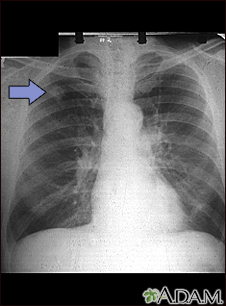

Adenocarcinoma - chest x-ray

This chest x-ray shows adenocarcinoma of the lung. There is a rounded light spot in the right upper lung (left side of the picture) at the level of the second rib. The light spot has irregular and poorly defined borders and is not uniform in density. Diseases that may cause this type of x-ray result would be tuberculous or fungal granuloma, and malignant or benign tumors.